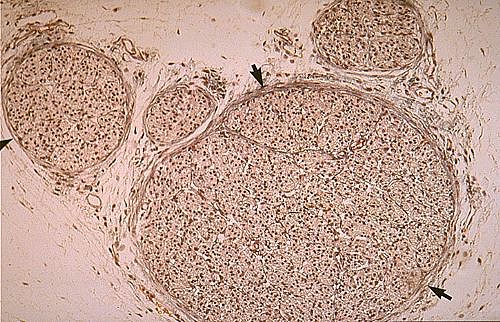

TP n°2 Le système nerveux central et périphérique / Observer - organiser

Nerf rachidien

Photo prise en TP Eléa, Théo D., Eva J., Dorian